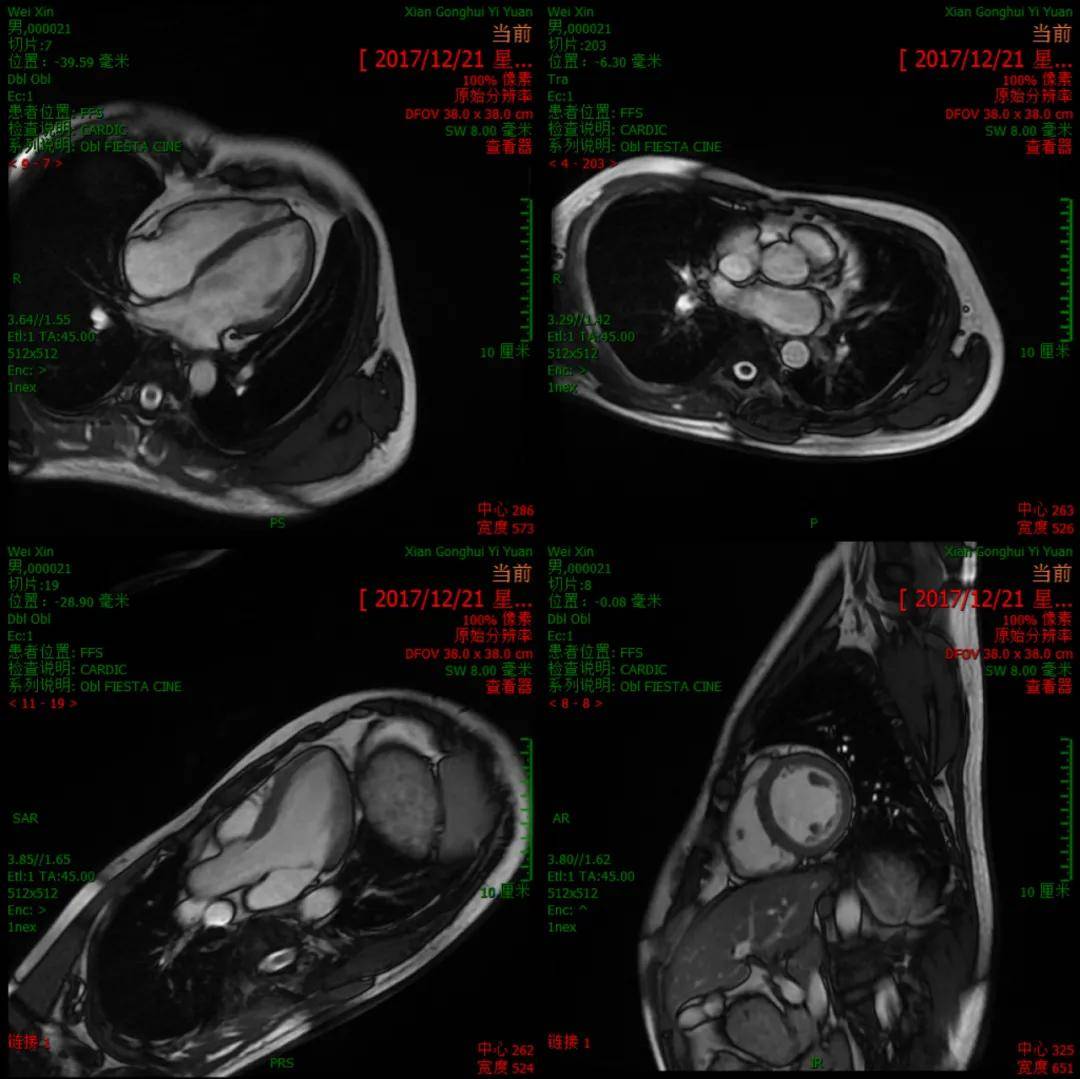

心脏MRI